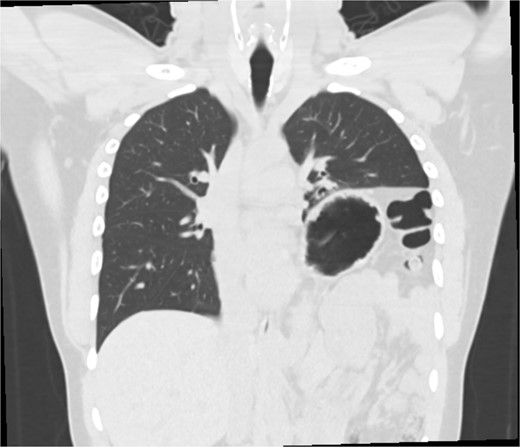

This is a case of a 26-year-old male patient who presented with symptoms of dyspnea on exertion, left chest pressure, and constipation for 7 years. He was a never smoker with no history of trauma, nor prior neck and chest surgeries. Baseline pulmonary functions tests revealed FEV1 of 71% predicted and DLCO of 77% predicted. Work-up included a computed tomography (CT) of the chest which revealed marked left hemidiaphragm elevation with compression atelectasis of the left lower lobe (Fig. 1). A fluoroscopic sniff test showed paradoxical movement of the left hemidiaphragm consistent with diaphragmatic paralysis. Interestingly, abdominal imaging obtained 14 months before surgery showed a displaced stomach but without volvulus (Fig. 2). Due to the impact on the patient’s quality of life, he was offered surgical treatment with a robotic-assisted left thoracoscopic plication of the diaphragm. This was done using a three-arm technique using the Da Vinci Xi surgical system (Intuitive Surgical, Sunnyvale, CA) with an additional assistant port. Plication was performed by placing multiple horizontal mattresses sutures reinforced with pledgets in an anterior–posterior orientation, and systematically working medial to lateral. A postoperative chest X-ray showed a satisfactory result (Fig. 3).

CT from 14-months pre-operation, demonstrating a full, but non-volvulized stomach.